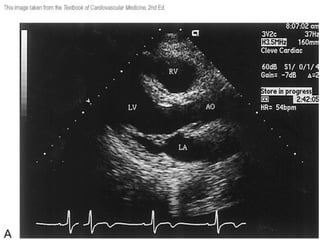

Examen bidimensional Eje largo : corre paralelo al corazón o al VI.  El eje corto  es perpendicular al eje largo. El  plano de 4 cámaras  es ortogonal a los otros dos  y de algún modo representa un plano frontal

Examen bidimensional Ejelargo : corre paralelo al corazón o al VI. El eje corto es perpendicular al eje largo. El plano de 4 cámaras es ortogonal a los otros dos y de algún modo representa un plano frontal